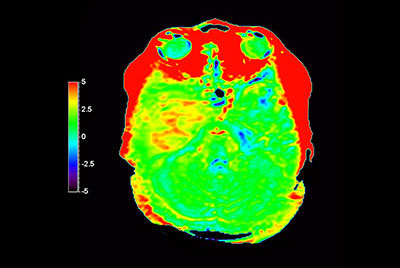

3D APT brain imaging for glioblastoma recurrence

-

Brain astrocytoma post radiotherapy, incl. 3D APT

-

Brain with glioblastoma, incl. 3D APT

-

Brain lesion with 3D APT

-